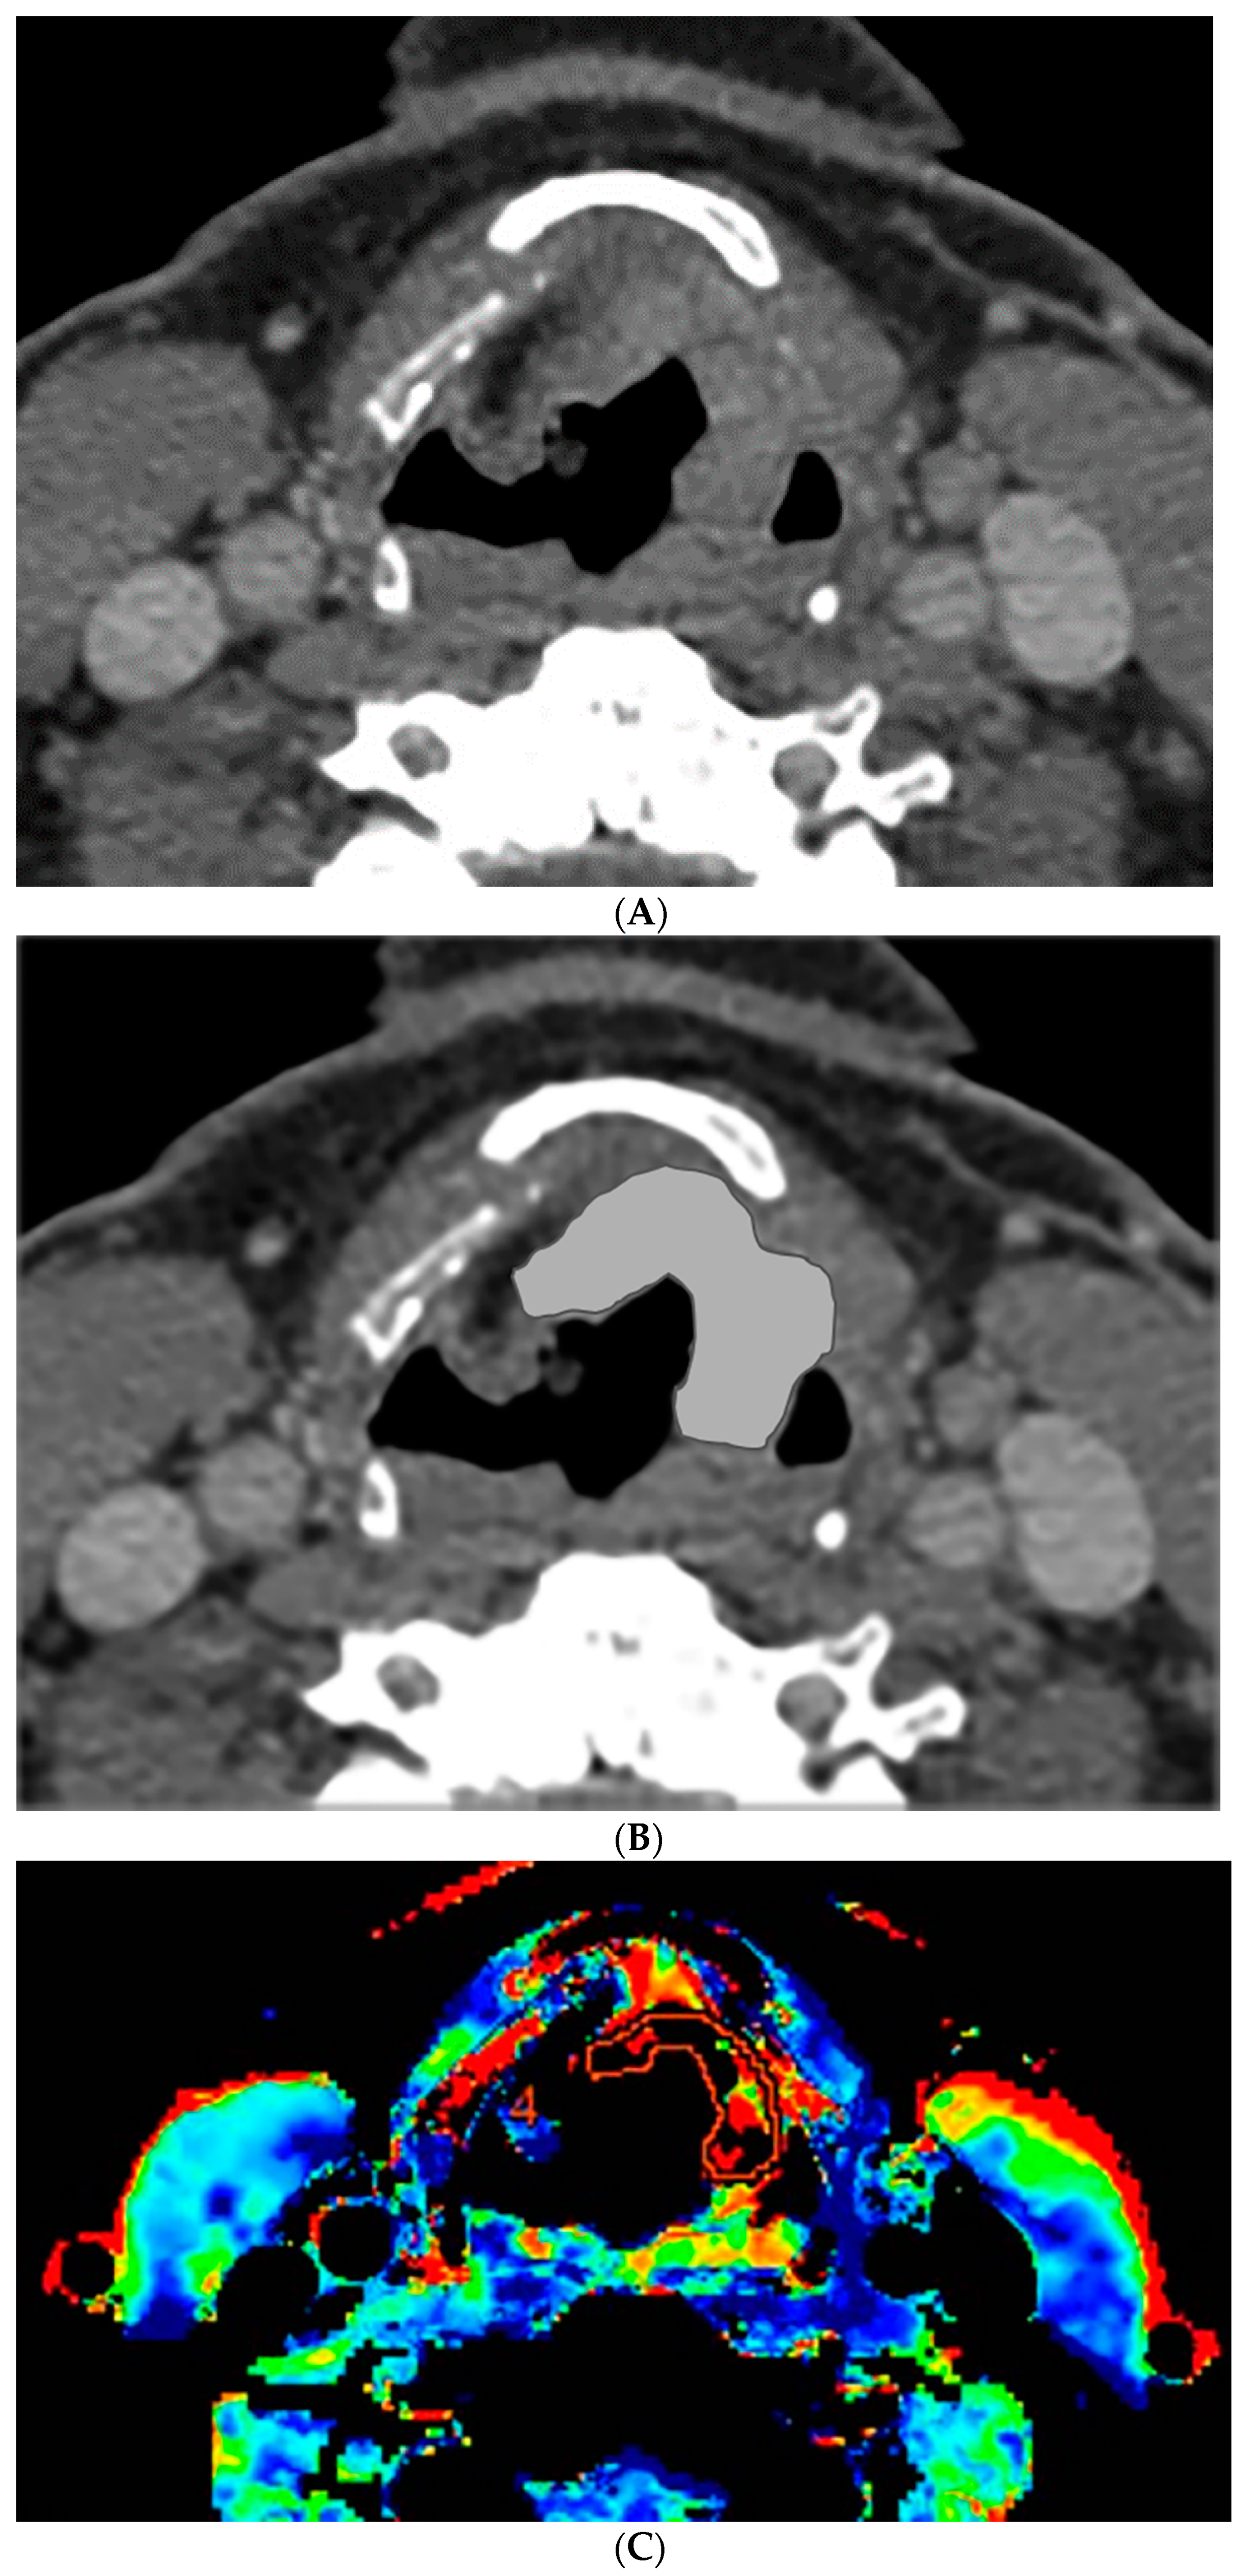

Figure 2.

CT and perfusion sections of laryngeal carcinoma on post-treatment images. Axial sections show the grayscale image (A) and outlines for the following: computer (B) and perfusion (C).

The percent volume change ICC of the computer with Radiologist 1 or Radiologist 2 were 0.80 and 0.74, respectively. The percent volume change ICC between the two radiologists was 0.73. The differences in the computer-versus-radiologist and radiologist-versus-radiologist ICCs did not achieve statistical significance. Examples of the semi-autonomous computerized 3D level-set segmentation are demonstrated in Figure 1 and Figure 2.